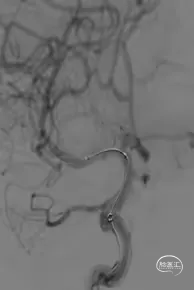

Synchro-14 300cm微导丝到位。

白驹颅内球囊扩张导管 2.0*15mm到位。

球囊扩张后管腔较前好转。

Enterprise-2 4.0mm*23mm支架释放。

正侧位造影提示管腔较前明显好转,支架贴壁良好,内血流通畅。